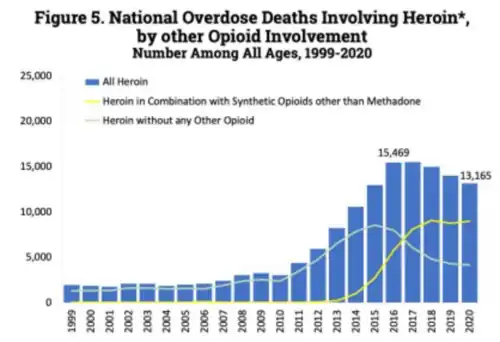

Between 2012 and 2015, heroin was the leading cause of drug-related deaths in the United States.[74] Since then, fentanyl has been a more common cause of drug-related deaths.[74]